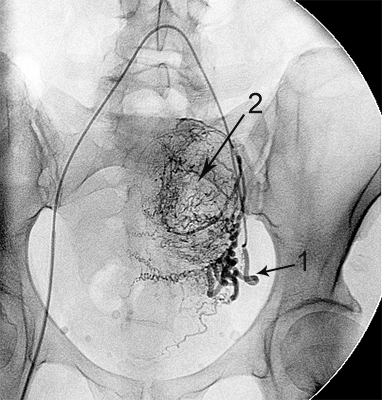

Ангіограми до та після емболізації:

міома матки до емболізації    міома матки після емболізації

Після емболізації частками: маткова артерія

збережена (1), лейоміома не контрастується (2).